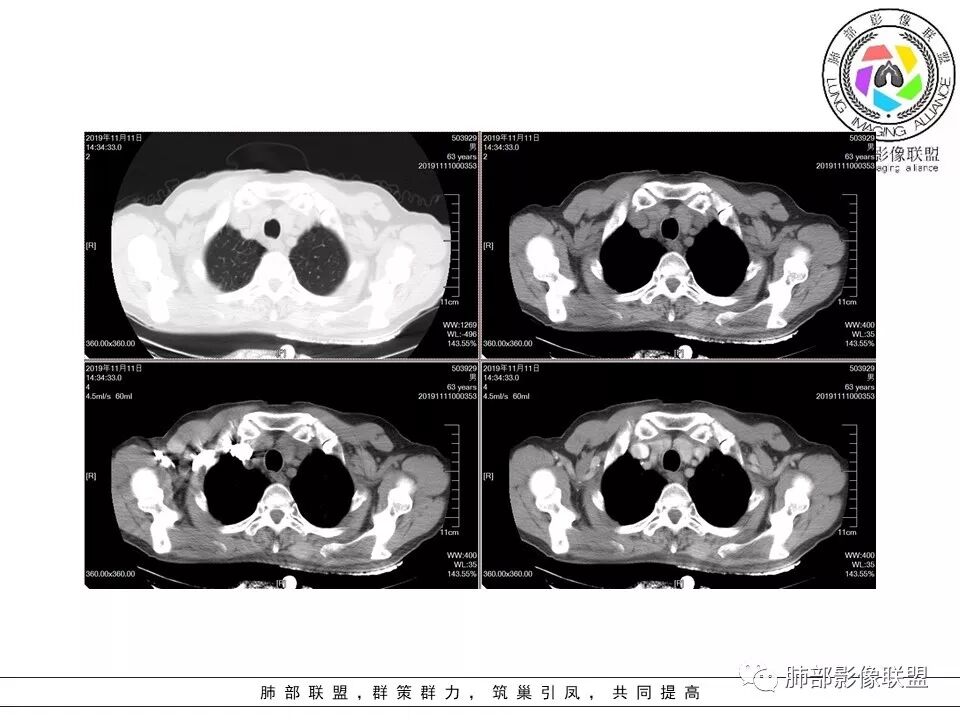

大雄:老年男性,有类风湿病史,长期服用激素,无阳性主诉CT示右肺上叶后段及左肺下叶基底段胸膜下多结节影,境界清晰,边缘毛糙,整体收缩,长轴与胸膜平行,增强扫描轻中度均匀强化。考虑炎性病变,建议查隐球荚膜多糖滴度试验

晕晕菜:患者中老年男性,体检发现肺部占位。既往既往有类风湿关节炎,长期口服激素胸CT:间隔旁肺气肿,右肺上叶后段胸膜下病变,与胸膜宽基底相连,局部胸膜明显增厚,病灶内可见空洞,病灶周围有散在卫星灶。左肺下叶背段胸膜下实变,病灶边界清楚,与长轴与胸膜平行,病灶周围可见软毛刺,纵隔窗可见病灶与胸膜呈糊墙征。 总体考虑良性病变。右上:结核?左下:隐球菌?

没意见:老年男性,明确有风免疾病背景,长期激素治疗,CT:双肺下叶外周多发结节,大部分宽基底胸膜相连,长轴垂直支气管,刀切平直,密度较为均匀,近心端空洞,强化程度目测略低,下肺背侧网格、磨玻璃、小蜂窝,考虑炎性结节,至于是感染还是风湿结节难度较大,需要结合临床来进一步确认

小赵:老年男性,类风湿及长期服药史。胸部CT所见右肺上叶及左肺下叶胸膜下多发病灶,右肺上叶病灶内见空洞及液平面,内壁光滑,周围散在条索及小结节样卫星灶,邻近胸膜增厚,增强扫描病灶轻度强化。左肺下叶病灶长轴平行于胸膜,周围见边界不清磨玻璃密度影,与邻近胸膜成糊墙改变。增强扫描病变成不均匀明显强化,内见强化血管影。诊断一元考虑双肺炎性病变,隐球菌可能。二元考虑右肺上叶结核,左肺下叶隐球菌感染,粘液腺癌待排。

菲菲菲:男,63,体检发现肺占位,既往类风湿性关节炎13年,双肺胸膜下多发斑片及结节影,右肺下叶病灶内见偏心性小空洞形成,周围有卫星灶,胸膜增厚,左肺下叶病灶轻度强化,纵隔内无肿大淋巴结,考虑炎性病变。隐球菌鉴别结核

破风5:胸部CT:右上叶胸膜下病变,与胸膜宽基底相连,累及胸膜,病灶内可见空洞,洞壁光滑,病灶周围有散在卫星灶。有类风湿激素口服历史,结核首先考虑。左肺下叶背段胸膜下实变,病灶边界清楚,与长轴与胸膜平行,血管伸入,纵隔窗可见糊墙征。考虑良性病变,隐球?总体,右上肺结核,左下肺隐球,CTD-ILD

流心明智:患者,老年男性,既往有类风湿关节炎,长期口服激素史。胸CT:间隔旁肺气肿,右肺上叶后段胸膜下病变,与胸膜宽基底相连,局部胸膜增厚,病灶内向肺门侧空洞,病灶周围卫星灶。考虑炎性病灶。左肺下叶胸膜下气肿背景边缘实变、边界清楚、有膨隆、滋养血管征,软毛刺、多结节融合、糊墙征。 总体考虑:良性病变,右上:结核?左下:隐球菌?左下鉴别Ca。

傅昌瑜:男,63,体检发现肺占位,既往类风湿性关节炎13年,RF升高,右下肺胸膜下结节,边缘多发斑片,右肺下叶病灶内见偏心性小空洞形成,相应层面胸膜增厚,左肺下叶两个结节,上面大点的结节位于胸膜下,似有支气管进入后截断,病灶轻度强化,病灶内见坏死区,纵隔内无肿大淋巴结。肺内病灶似乎不怎么类似,隐球菌应该是兄弟同心。肺内病灶考虑肉芽肿性病灶,有长期口服糖皮质激素史,首先考虑奴卡可能,鉴别隐球菌及结核这个妖怪。类风湿结节没有见过。

初学者:支持。。。类风湿关节炎,那么肺内表现的是间质性肺炎,这个没有问题。现在就是看这些结节和团块是什么。患者有哪些危险因素:1.类风湿关节炎:类风湿结节 2.因为激素治疗,熊大说激素就是小艾滋,那么会容易得得:隐球菌,结核,PCP等等。3.间质性肺炎本身就容易发生肿瘤。所以目前我们需要考虑得三个方向:类风湿结节,肉芽肿性炎,或肿瘤。三者鉴别